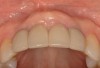

Fig 9. Completed crowns at 5 years, front view. Implant No. 9 was screw-retained (periodontist: Robert A. Levine, DDS; restorative dentist: Zola Makrauer, DMD).

Figure 9

Fig 10. Completed crowns at 5 years, angled view. Note the convex contours facial to implant No. 9 attributed to the connective tissue grafting.

Figure 10

Figure 8 shows the provisionalization of No. 8 at 6 weeks postoperatively and a screw-retained provisional restoration on No. 9 to develop the subgingival transitional zone (key Nos. 8 through 10). The transitional zone will be duplicated using the custom impression coping technique. Figure 9 and Figure 10 depict the completed crowns at 5 years; implant No. 9 was screw-retained (key No. 10). In Figure 10 note the convex contours facial to implant No. 9 that are attributed to the connective tissue grafting as part of the surgical protocol creating biotype conversion from a thick to a thicker biotype. Figure 11 through Figure 13 show 5-year postoperative patient smile, periapical x-ray, and CBCT, respectively.